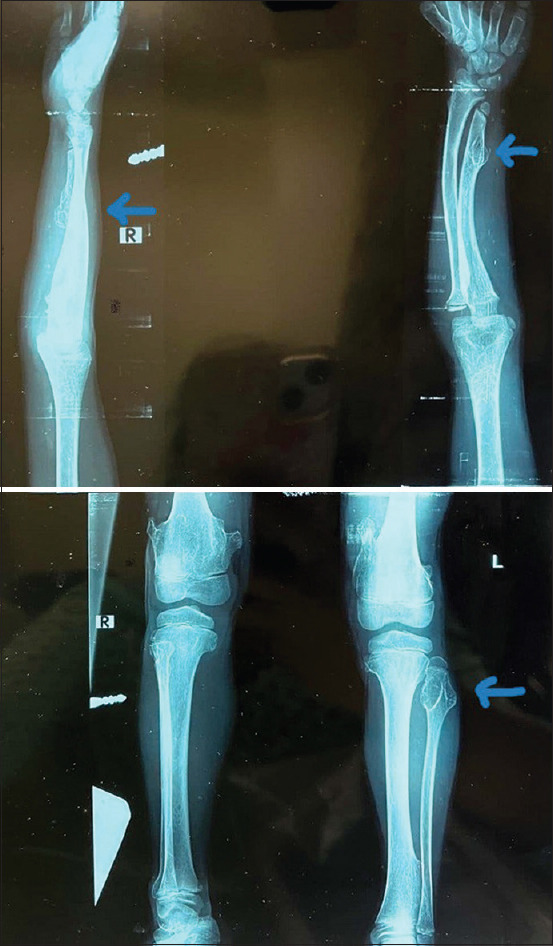

Methods: HME is an autosomal dominant genetic disease characterized by the presence of multiple exostoses (osteochondromas). It is caused by mutations in two genes: exostosin-1 (EXT1) and exostosin-2 (EXT2). We report HME in a family over three generations. The index case was a 14-year-old female who presented with an ocular mass and multiple hard nodules in the upper and lower limbs. Family history revealed similar multiple nodules in the younger brother, father, and grandfather. Hence, the paternal family history for HME is positive. All the family members were examined. Family members who were diagnosed with HME had a series of radiology tests completed. Furthermore, the family members with HME were also seen by an orthopedic surgeon.

Results: Family history and physical examination revealed multiple exostoses in the younger brother, father, and grandfather. They were all diagnosed with HME. The index case also had an ocular surface mass with scleral ectasia in the right eye.